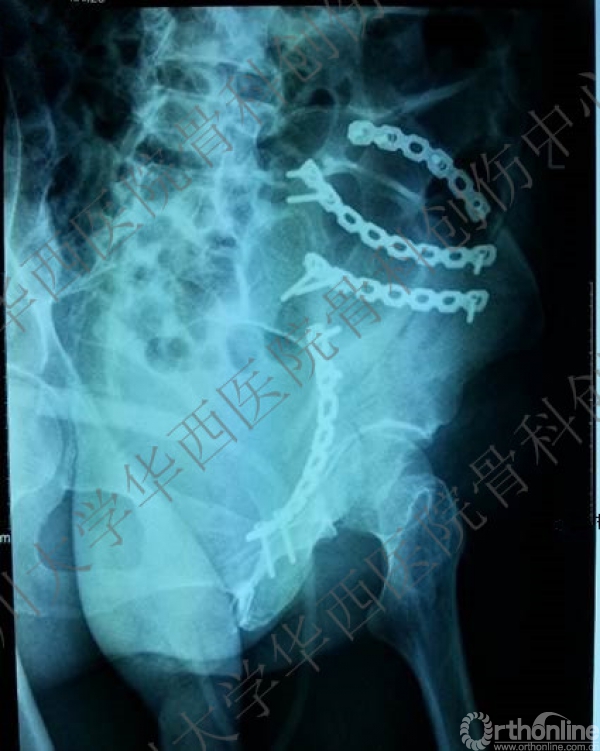

术后X线片

这是术后的X线片,患侧正位、髂骨斜位、闭孔斜位。

术后三维重建

术后三维重建前面观完美!

术后三维重建后面观,发现后壁的骨折有明显的移位,后脱位的风险增加,我们决定!

3天后

3天后,行后路切开复位内固定术。